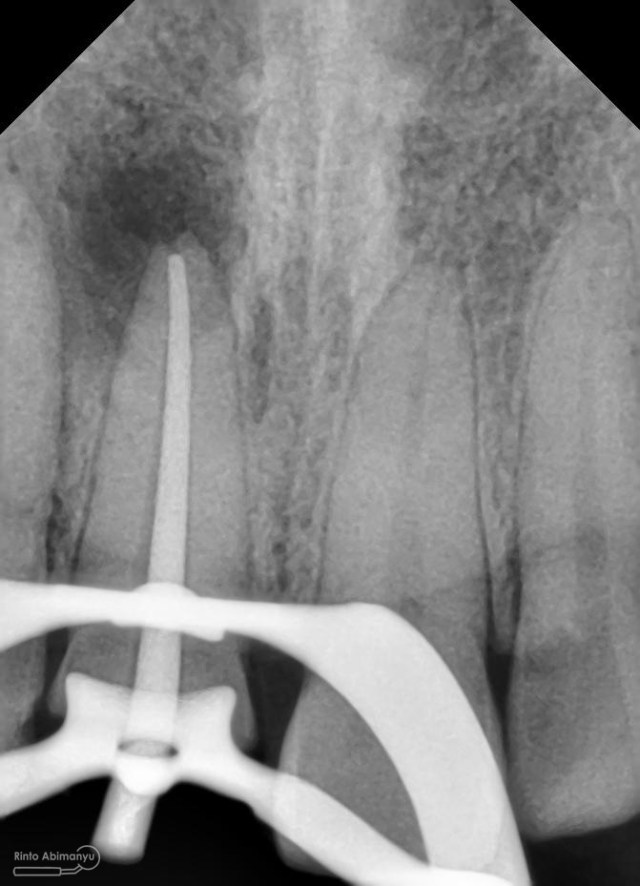

dan ini foto ronsen nya…

Foto radiografis gigi 11 21 22 yang mengalami fraktur

Dari pemeriksaan radiografis lokasi fraktur menyerempet kamar pulpa pada ketiga gigi tersebut… Saya sampaikan kepada pasien bahwa ketiga gigi tersebut memerlukan perawatan saluran akar terlebih dahulu baru kemudian dilanjutkan dengan restorasi indirek… kenapa saya pilih restorasi indirek? Pertimbangannya adalah sisa struktur mahkota gigi yang ada bila hanya di “sambung” dengan restorasi direk dalam jangka panjang rentan mengalami kerusakan, yang kedua pemilihan warna akan lebih maksimal pada kasus ini…. Pasien setuju dengan rencan perawatan yang saya jelaskan…